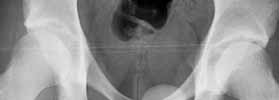

I believe this patient has anterior hip impingement caused by a retroverted acetabulum. This is seen on the submitted AP x-ray by observing the overlap of the anterior wall and posterior wall. In an acetabulum with "normal" version, the anterior wall shadow meets the posterior wall shadow at the superio- lateral aspect of the acetabulum, and they do not overlap as you follow the lines inferiorly. In an acetabulum with retroversion, the two shadows cross over the femoral head, making a figure 8 pattern.

To further confirm this, obtain a full AP pelvis film and a false profile view of both hips. In addition, the patient has an element of hip dysplasia, seen by his decreased center edge angle. On physical exam, his pain will be reproduced by hip flexion, adduction and internal rotation, when the anterior surface of the femoral neck impinges on the anterior labrum and wall. An MRI may show hypertrophic changes in the femoral neck. I also recommend a gadolinium MRI hip arthrogram to ensure there is no significant labral pathology.

Here are some pictures from a case where the femoral head was surgically dislocated and trimmed for acetabular and femur impingment syndrome.

The technique is described by Ganz and Mast as a digastric approach (trochanter flip osteotomy) to the hip joint without destroying blood supply to the femoral head. The approach may also be applied to some acetabular fractures.